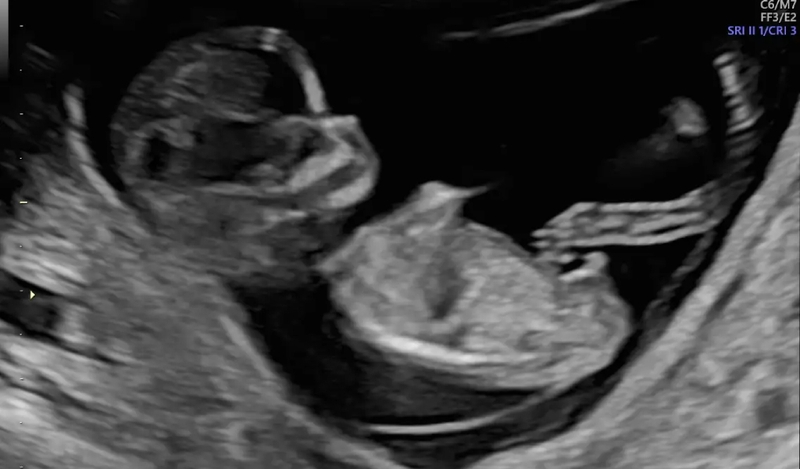

Siêu âm 12 tuần đã biết trai hay gái chưa?

Siêu âm 12 tuần sẽ chưa thể xác định chính xác giới tính của thai nhi. Bởi vì việc này còn phụ thuộc vào mức độ phát triển bộ phận sinh dục và vị trí nằm của trẻ. Ngoài ra, cân nặng của người mẹ, chất lượng phim chụp và tay nghề của bác sĩ cũng ảnh hưởng không nhỏ đến khả năng dự đoán.

Mặc dù thai nhi lúc 12 tuần tuổi đã xuất hiện cơ quan sinh dục nhưng vẫn chưa thể cho ra kết quả chính xác. Sau đây là các mốc thời gian mà bạn có thể nhìn hình siêu âm đoán giới tính thai nhi:

• Từ 10 - 12 tuần tuổi: Có thể dự đoán chính xác từ 50 - 70%;

• Từ 12 - 16 tuần tuổi: Kết quả dự đoán chính xác khoảng 80%;

• Từ 16 tuẩn tuổi trở lên: Bạn có thể dự đoán chính xác giới tính thai nhi gần như tuyệt đối.

Để biết thai nhi là trai hay gái, bạn nên nhìn vào hình ảnh giữa hai háng. Nếu bạn nhìn thấy ba vạch song song là nữ, còn nếu nhìn thấy dương vật thì thai nhi là nam.

Giải đáp thắc mắc: Siêu âm 12 tuần đã biết trai hay gái chưa 2 Siêu âm 12 tuần đã biết trai hay gái chưa? Chỉ có thể dự đoán được từ 50 - 70%